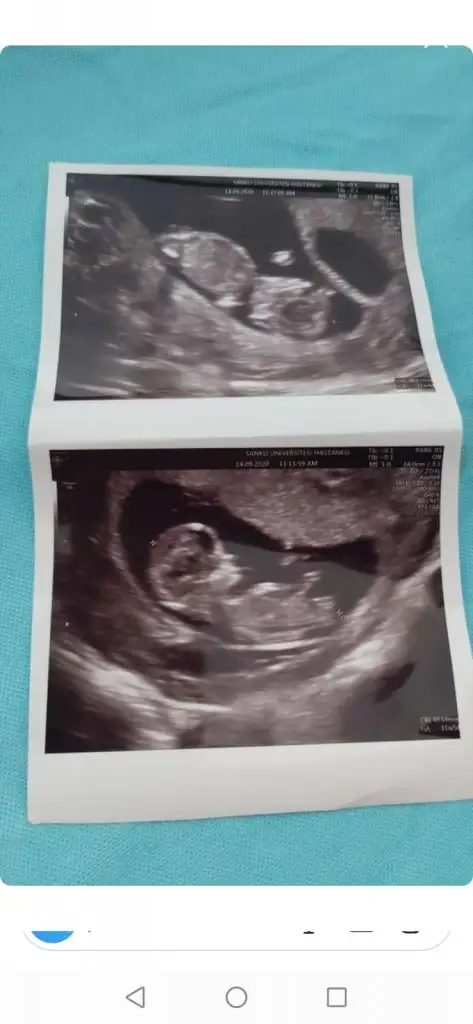

Kaç haftalık USG 11 12 13 haftalar olmalı sanki kız gibi emin olamadımIkra meyra merhaba, bakabilir misiniz acaba kız mı erkek mi? 14 haftalıkken. göstermedi hala kendini merk ettik :)

14. HaftadanKaç haftalık USG 11 12 13 haftalar olmalı sanki kız gibi emin olamadım

Çok net değil üsteki sanki kız altaki erkek gibi diyecem emin olamadım başka USG varsa paylaşınMerhaba arkadaşlarımın ikizlerini de yorumlar mısınız 12. HaftadalarEki Görüntüle 2698252